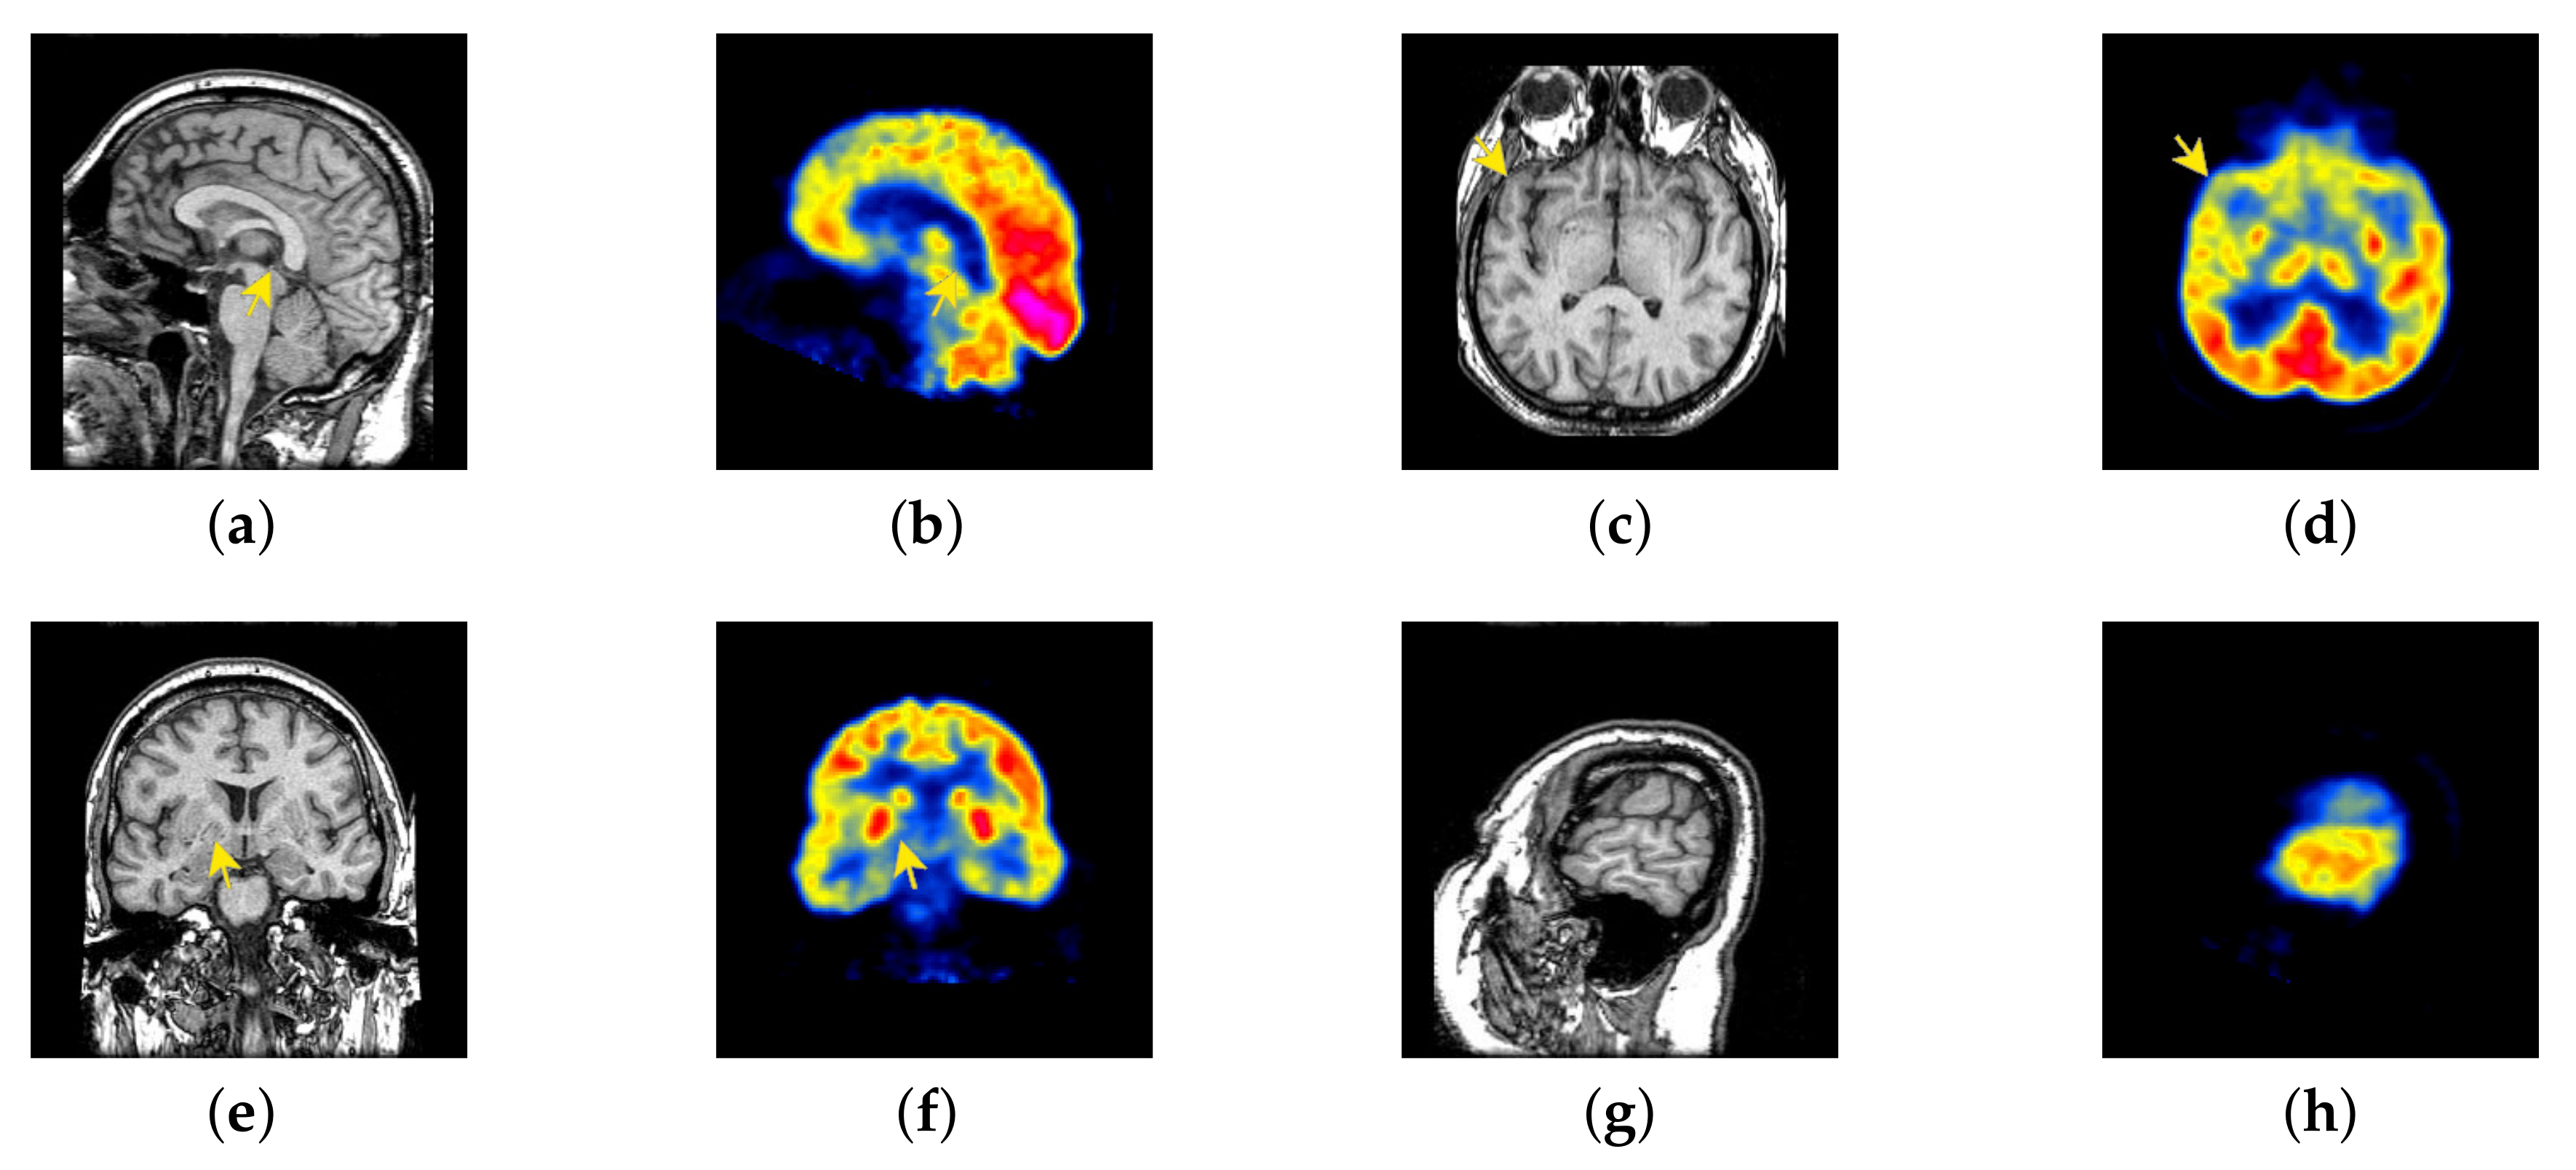

4.4. The Fusion of MRI-CBF

Cerebral blood flow diagram (CBF), which indicates the amount of blood flow in brain tissue with color. Red, yellow, green, blue, and black successively indicate the amount of blood flow from more to less. It is mainly used to detect the blood flow supply condition, elasticity, tension, and peripheral resistance. However, with the development of medical science, CBF image is often inferior in the diagnosis of brain diseases due to its lack of structural information. Therefore, MRI which is good at expressing structural information, is introduced to fuse in the current trend of brain medicine.

In this section, there are four image sets to fuse, each containing a MRI image and its corresponding CBF image in Figure 41. In Figure 42, Figure 43, Figure 44 and Figure 45, it can be seen that the structural information of fusion images obtained by our algorithm is complete. The color is not distorted, and the spectral features are natural. The fusion image based on DTCWT and NSCT algorithm have high color fidelity but less structural information. Other algorithms, such as IGM, LPSR, and FusionCNN, only focus on the structural information of the MRI image and ignore the color information of the fused image. Although the image structure information obtained by DDcGAN fusion algorithm is relatively complete, the edge of color information is not clear, which has a great influence on image contrast.

Figure 41.

Four pairs of MRI-cerebral blood flow diagram (CBF) source images: (a,c,e,g) are MRI images; (b,d,f,h) are CBF images.

Figure 42.

Fused medical images obtained by different algorithms (Figure 41a,b): (a) DTCWT, (b) GFF, (c) NSCT, (d) LPSR, (e) IGM, (f) FusionCNN, (g) DDcGAN, and (h) FusionNet.

Figure 43.

Fused medical images obtained by different algorithms (Figure 41c,d): (a) DTCWT, (b) GFF, (c) NSCT, (d) LPSR, (e) IGM, (f) FusionCNN, (g) DDcGAN, and (h) FusionNet.

Figure 44.

Fused medical images obtained by different algorithms (Figure 41e,f): (a) DTCWT, (b) GFF, (c) NSCT, (d) LPSR, (e) IGM, (f) FusionCNN, (g) DDcGAN, and (h) FusionNet.

Figure 45.

Fused medical images obtained by different algorithms (Figure 41g,h): (a) DTCWT, (b) GFF, (c) NSCT, (d) LPSR, (e) IGM, (f) FusionCNN, (g) DDcGAN, and (h) FusionNet.